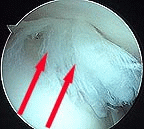

Arthroscopy Pictures of a Partial Rotator Cuff Tear

After removal of devitalized tissue